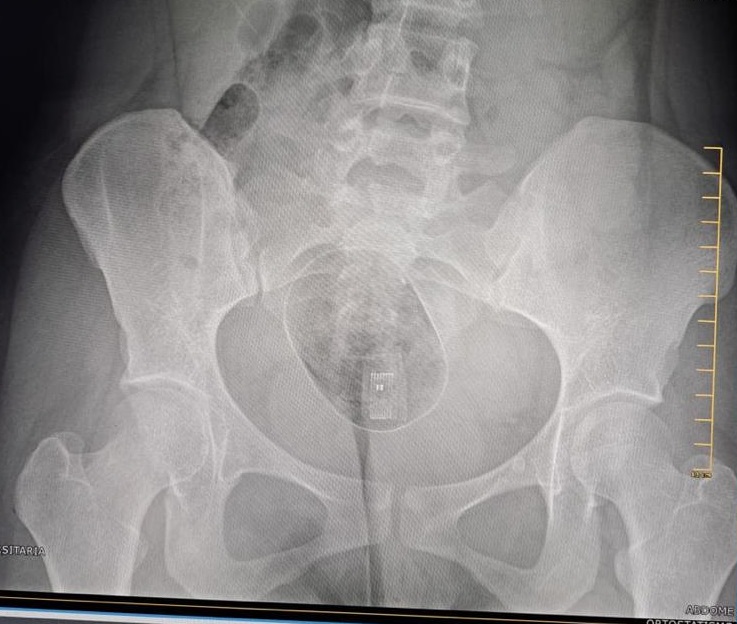

Segundo informações da Seris, a mulher de iniciais J. H. G. A. foi flagrada com o entorpecente e o aparelho enquanto passava pelo body scan, equipamento usado para fazer varredura corporal interna nos visitantes. Mesmo após conseguir retirar a droga e o pen drive, ela ficou com um pacote dentro do corpo e precisou ser encaminhada a uma unidade de saúde. No local, o médico que a atendeu avaliou que a mulher vai precisar passar por procedimento cirúrgico para a remoção do pacote.

A mulher está sendo acompanhada pela polícia e a cirurgia deve acontecer no Hospital Geral do Estado. Após o procedimento, ela deve ser submetida a uma audiência de custódia, para saber se permanece detida ou se vai responder o processo em liberdade.